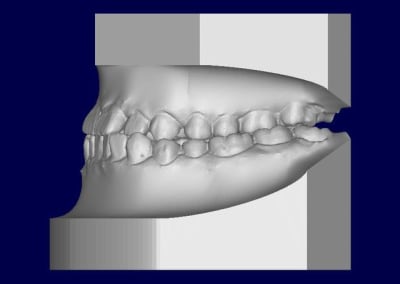

Patient asiatique, 25 ans, consulte car il veut corriger son crossbite bite antérieur localisé aux latérales et son crossbite secteur 2/3. Il aimerait également corriger son apparence générale, son profil notamment.

Classe III squelettique et dentaire.

Pas de shift à la fermeture.

Ci joints photos, ceph, modeles.